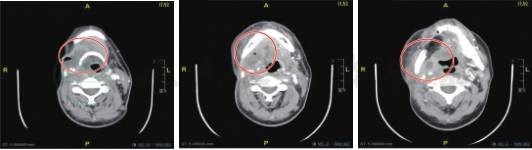

2018-12-11颌面部增强CT提示:术区、右侧颈鞘区、颌下、口咽占位(肿瘤复发),右腮腺下极、咽后、左侧颈上转移淋巴结可能(图1)。

图1 术区、右侧颈鞘区、颌下、口咽占位(肿瘤复发),右腮腺下极、咽后、左侧颈上转移淋巴结可能(皮瓣后缘及下方、右颌下、颈鞘区、右侧口咽壁见软组织肿块,增强后边缘强化,右侧颈内动脉基本受包绕,右腮腺下极、咽后、左侧颈上见环形强化淋巴结影)